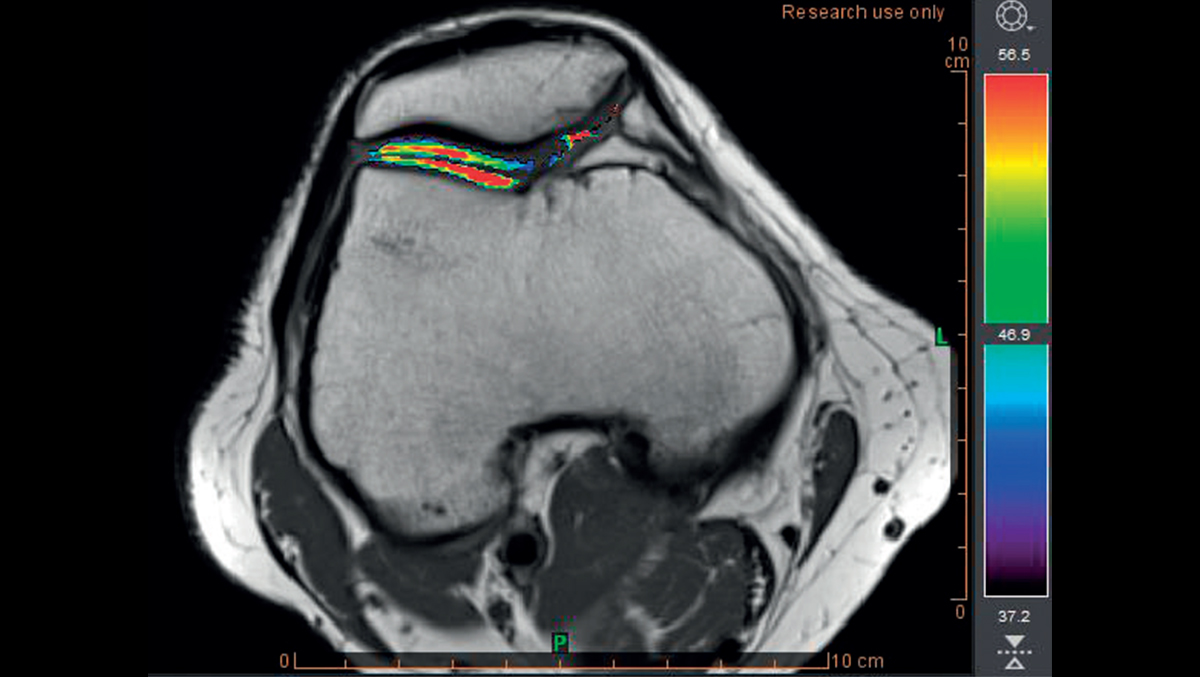

Опорно-двигательный аппарат

Диагностика и наблюдение за спортивными и ортопедическими заболеваниями

- Расчет отображения T2

- Раннее обнаружение разрушения хряща с помощью карты Thresholds T2

Обнаружение хрящевой ткани в группе риска с использованием пороговых значений времени релаксации T2